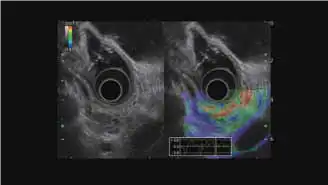

与电子环扫超声内镜配套使用

COLOR FLOW模式 THE-R模式 ELST模式